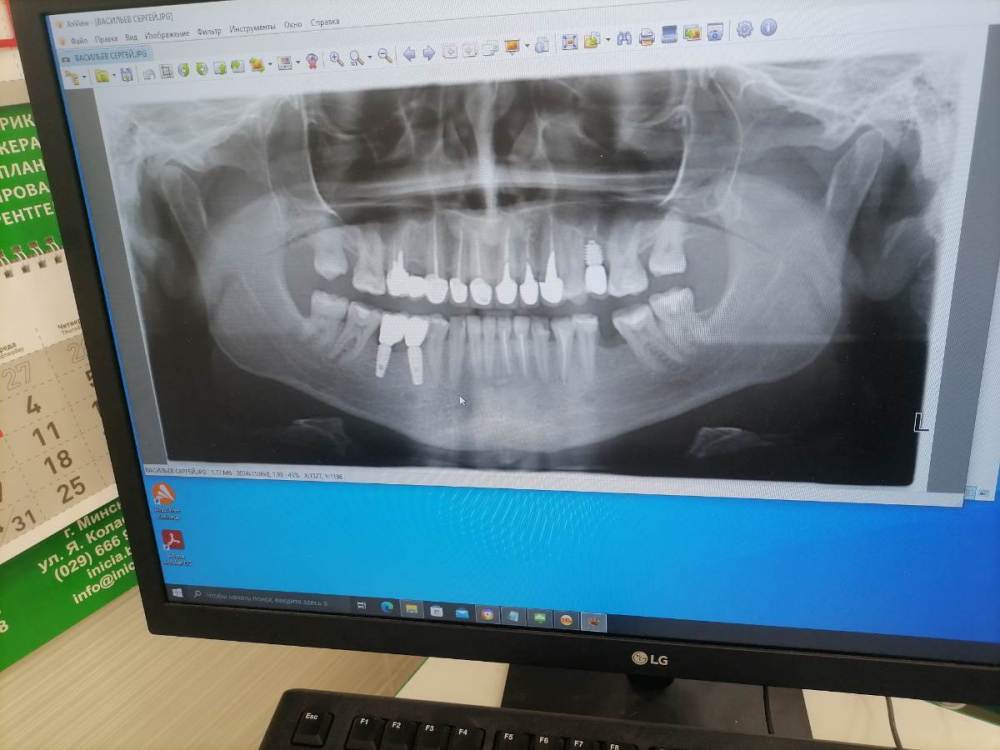

Добрый день уважаемые доктора. После установки коронок на импланты, беспокоит что на контрольном снимке оголилось 2 витка резьбы импланта.

Сами импланты установлены в ноябре.  Коронки на них поставили месяц  назад, закрутили с усилием 25 ньютонов, и поставили временную пломбу . Отправили на месяц гулять. Сегодня сделал снимок, пришёл к врачу врач сказала что все отлично. Докрутила на 35 и поставила постоянную пломбу. Но меня беспокоит что ушло несколько витков резьбы, хотелось бы услышать ваше мнение, скажите это нормально? По ощущениям ничего не беспокоит, жую без проблем.